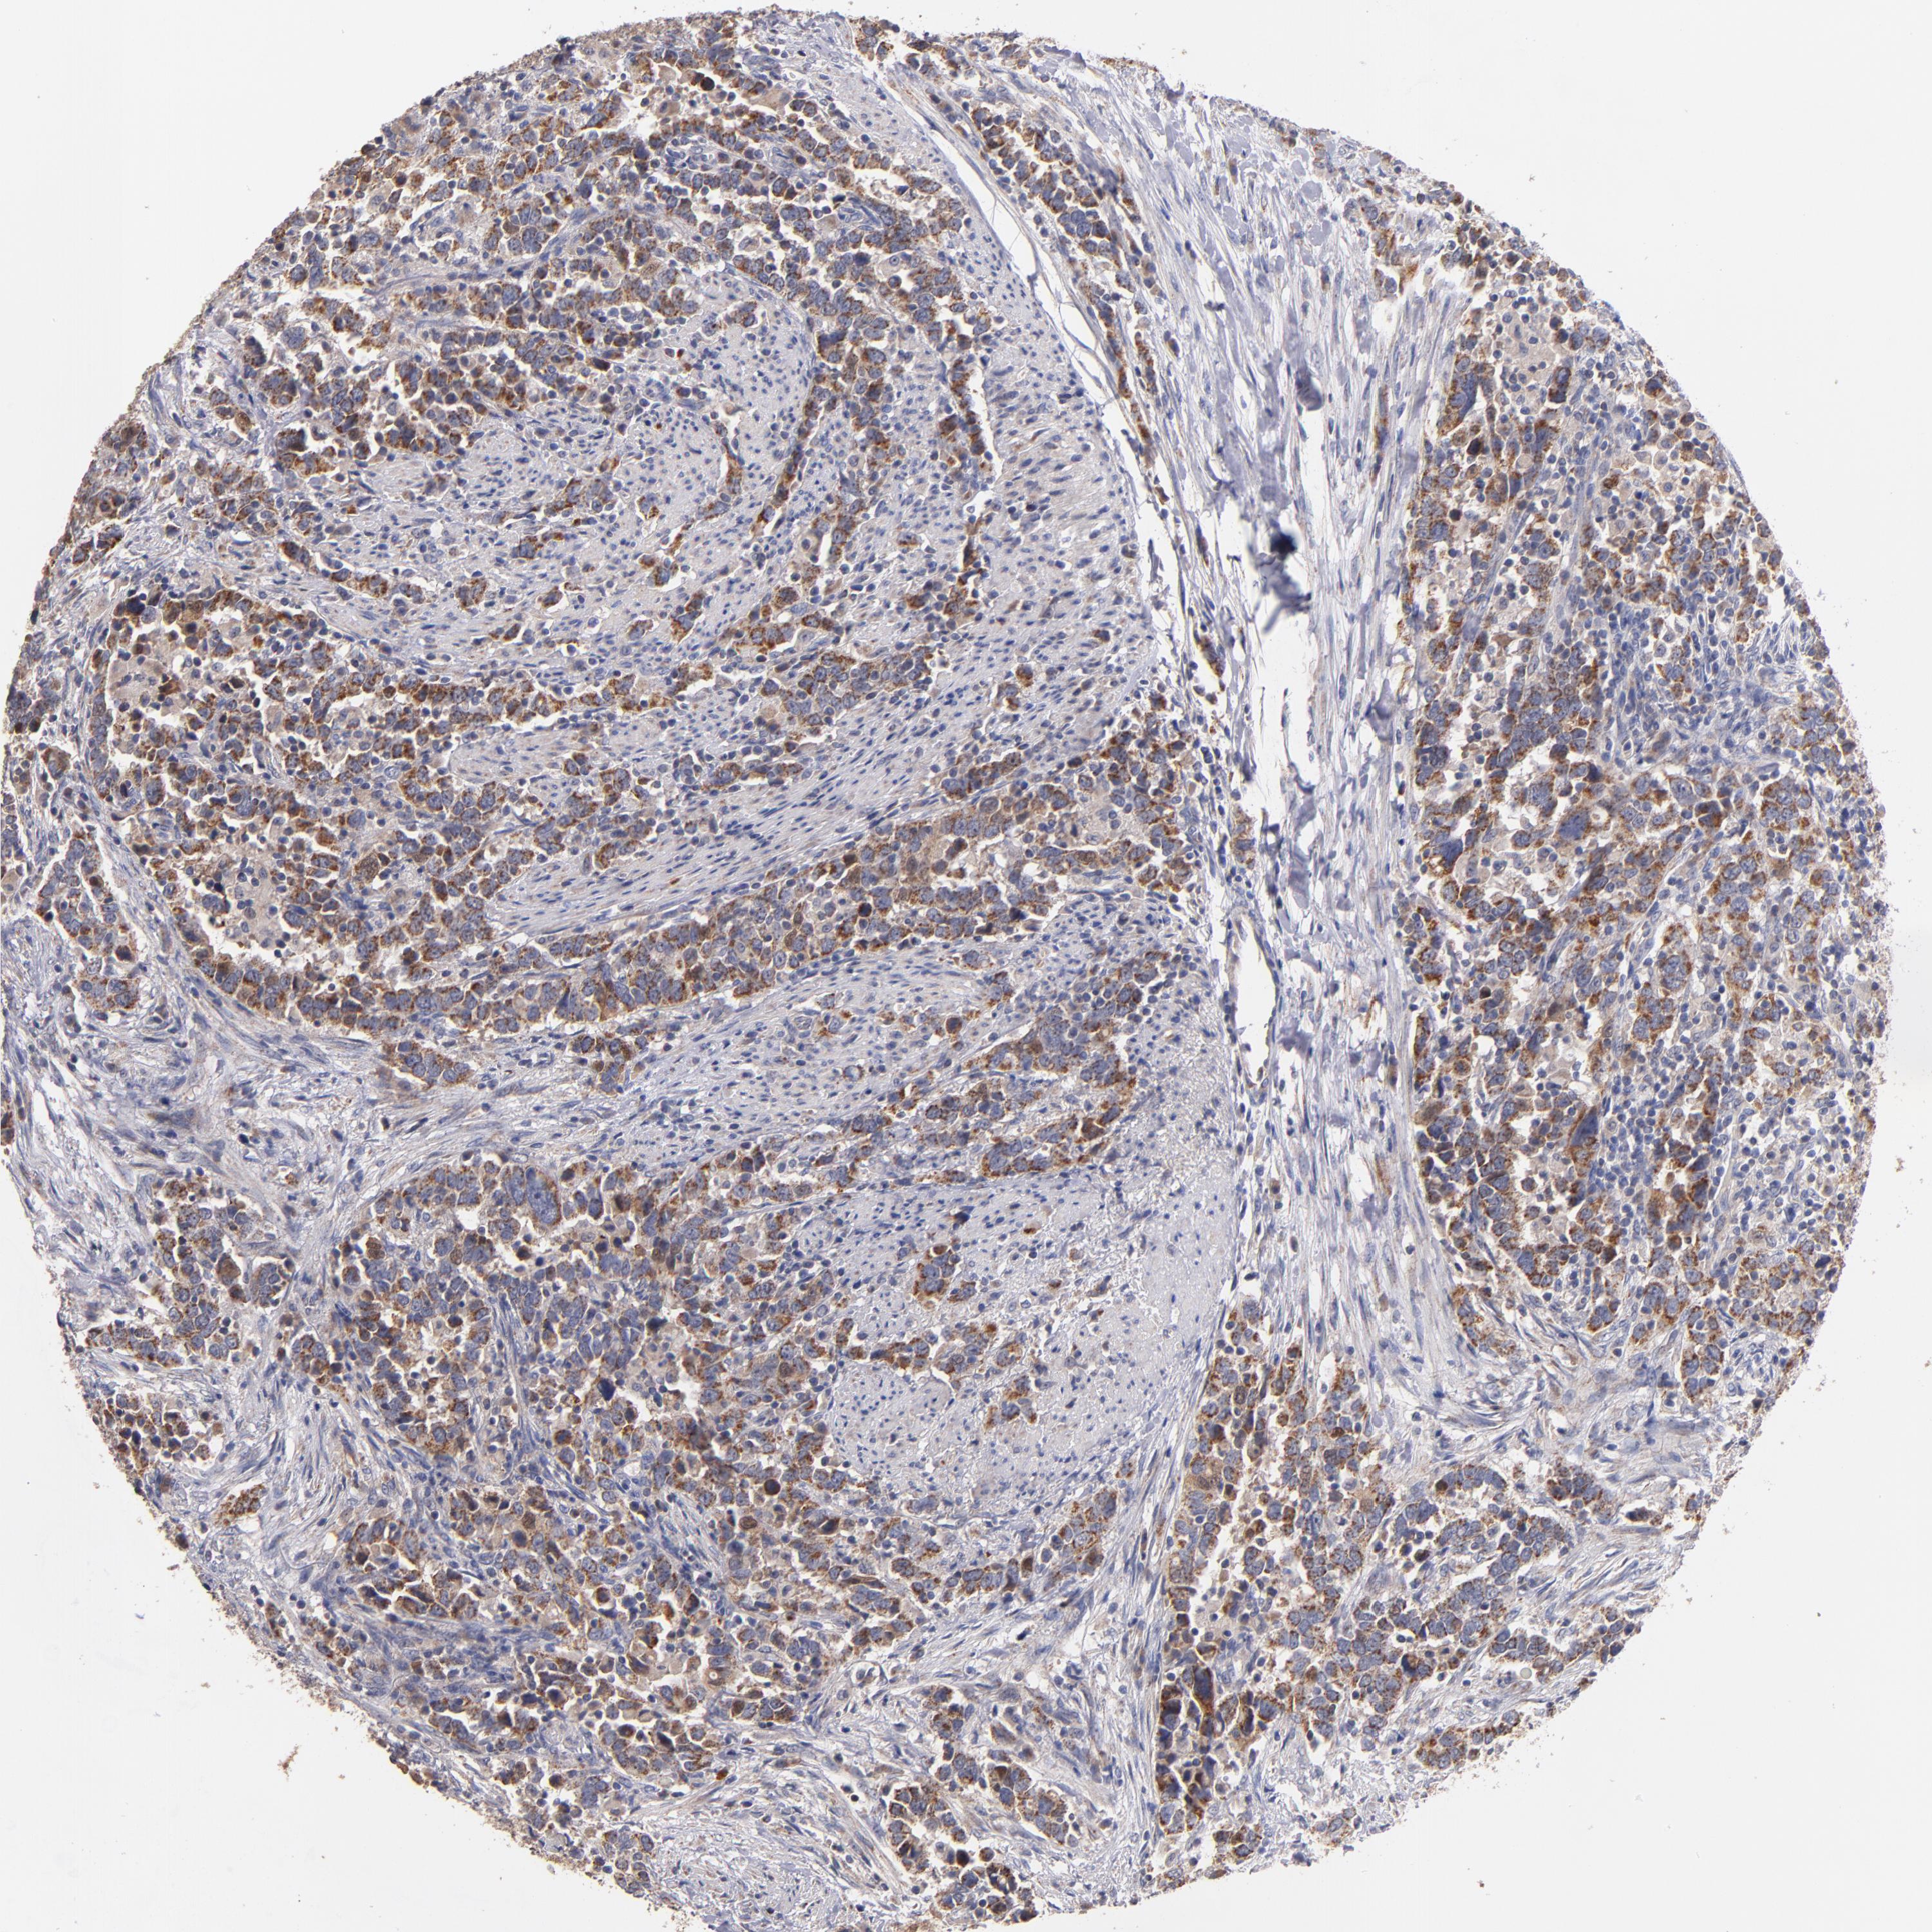

UROTHELIAL CANCER - Protein expressioni

A mouse-over function shows sample information and annotation data. Click on an image to view it in a full screen mode. Samples can be filtered based on level of antibody staining by selecting one or several of the following categories: high, medium, low and not detected. The assay and annotation is described here.

Note that samples used for immunohistochemistry by the Human Protein Atlas do not correspond to samples in the TCGA dataset.

Antibody stainingi

Antibody staining in the annotated cell types in the current human tissue is reported as not detected, low, medium, or high, based on conventional immunohistochemistry profiling in selected tissues. This score is based on the combination of the staining intensity and fraction of stained cells.

Each image is clickable and will lead to virtual microscopy that enables deeper exploration of all samples and also displays staining intensity scores, fraction scores and subcellular localization as well as patient and tissue information for each sample.

Antibody HPA001825

Antibody CAB003857

Urothelial carcinoma, High grade

Urothelial carcinoma, Low grade